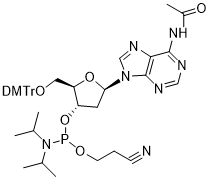

馬鞍山致研生物醫(yī)藥科技有限公司成立于馬鞍山市鄭浦港新區(qū)現(xiàn)代產(chǎn)業(yè)園。公司專(zhuān)注于生物小分子、醫(yī)藥中間體相關(guān)產(chǎn)品的研發(fā)和生產(chǎn),產(chǎn)品主要包括DNA亞磷酰胺單體、RNA亞磷酰胺單體、特殊單體以及按照客戶(hù)要求定制的RNA和DNA,并且公司提供定制合成等方面的研究服...

馬鞍山致研生物醫(yī)藥科技有限公司成立于馬鞍山市鄭浦港新區(qū)現(xiàn)代產(chǎn)業(yè)園。公司專(zhuān)注于生物小分子、醫(yī)藥中間體相關(guān)產(chǎn)品的研發(fā)和生產(chǎn),產(chǎn)品主要包括DNA亞磷酰胺單體、RNA亞磷酰胺單體、特殊單體以及按照客戶(hù)要求定制的RNA和DNA,并且公司提供定制合成等方面的研究服...